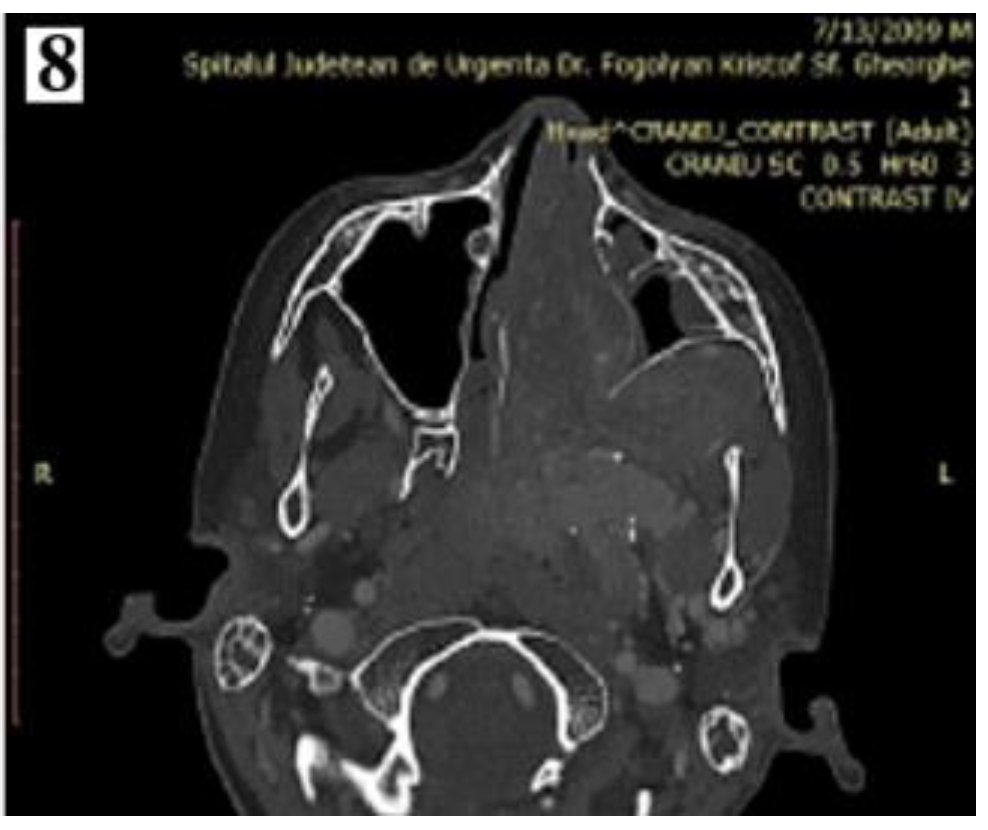

Figure 6. IIA—Minimal lateral extension into the pterygopalatine fossa; IIB—Full occupation of pterygopalatine fossa with or without superior erosion orbital bones (part 2).

For stages IIA-IIB, the trans-nasal surgery is indicated, following the same steps as for stages IA and IB.

Figure 5. IIA—Minimal lateral extension into the pterygopalatine fossa; IIBFull occupation of pterygopalatine fossa with or without superior erosion orbital bones (part 1).